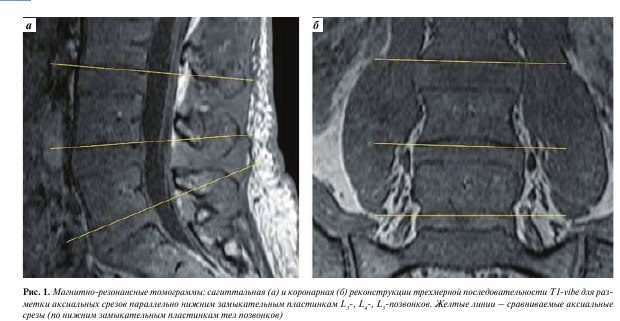

Изображения, полученные с помощью вышеописанной последовательности T1-vibe без жироподавления, открывали в программе InobitecPro в режиме мультипланарной реконструкции, где строились аксиальные срезы, параллельные в коронарной и сагиттальной проекциях нижним замыкательным пластинкам L3-, L4-, Ь5-позвонков (рис. 1). На построенных изображениях на всех 3 уровнях с помощью инструмента «ROI полигон» обводили многораздельные мышцы с обеих сторон, как показано на рис. 2 (вдоль границы остистого и суставного отростков, затем по фасции многораздельной мышцы), для оценки средней интенсивности сигнала и площади выделенной зоны. Кроме того, в режиме T1-vibe без жироподавления с помощью инструмента «ROI овал» измеряли среднюю интенсивность сигнала в жировой клетчатке слева от паравертебральных мышц (см. рис. 2).